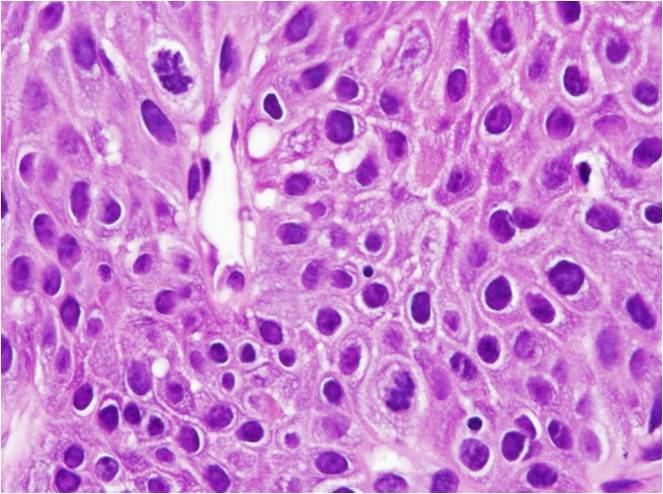

显微镜下见鳞状上皮增生伴棘层增厚和表层不全角化,增厚的上皮向上延伸而不向下延伸到固有层,上皮钉突变宽,常汇合在一起,有时呈球棒状。表浅棘层细胞常见凹空细胞样改变。有时可见表层细胞细胞核呈有丝分裂样改变,称为有丝分裂样细胞。固有层常较疏松,血管丰富,有不同程度淋巴细胞浸润。

高倍镜显示有丝核分裂样细胞